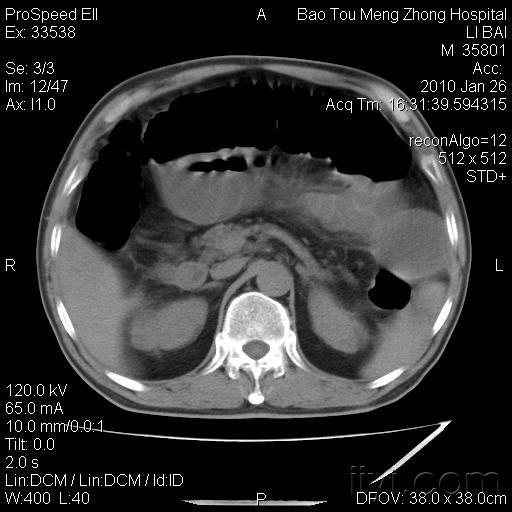

∩0∩ 急性阑尾炎别慌,不一定非得挨那一刀!急性阑尾炎的病理分型:决定治疗方向的关键 急性阑尾炎根据病理改变可分为不同类型,而类型差异直接影响治疗方式的选择。单纯性阑尾炎,炎症往往局限在阑尾黏膜和黏膜下层,阑尾外观可能仅表现为轻度肿胀,色泽稍显充血。此时,阑尾的病变相对较轻,尚未形成严重的化脓、坏疽或穿...

腹部剧烈疼痛竟是急性阑尾炎!医生:3个信号别忽视,早发现早治如果是症状较轻的单纯性阑尾炎,在医生评估后可以用抗生素进行保守治疗;但如果发展成化脓性、坏疽性阑尾炎,或者有穿孔的风险,及时手术切除阑尾就是最安全的选择。要知道,阑尾一旦穿孔,里面的细菌和脓液会扩散到整个腹腔,引发腹膜炎,严重时还可能导致感染性休克,后果不堪设想...